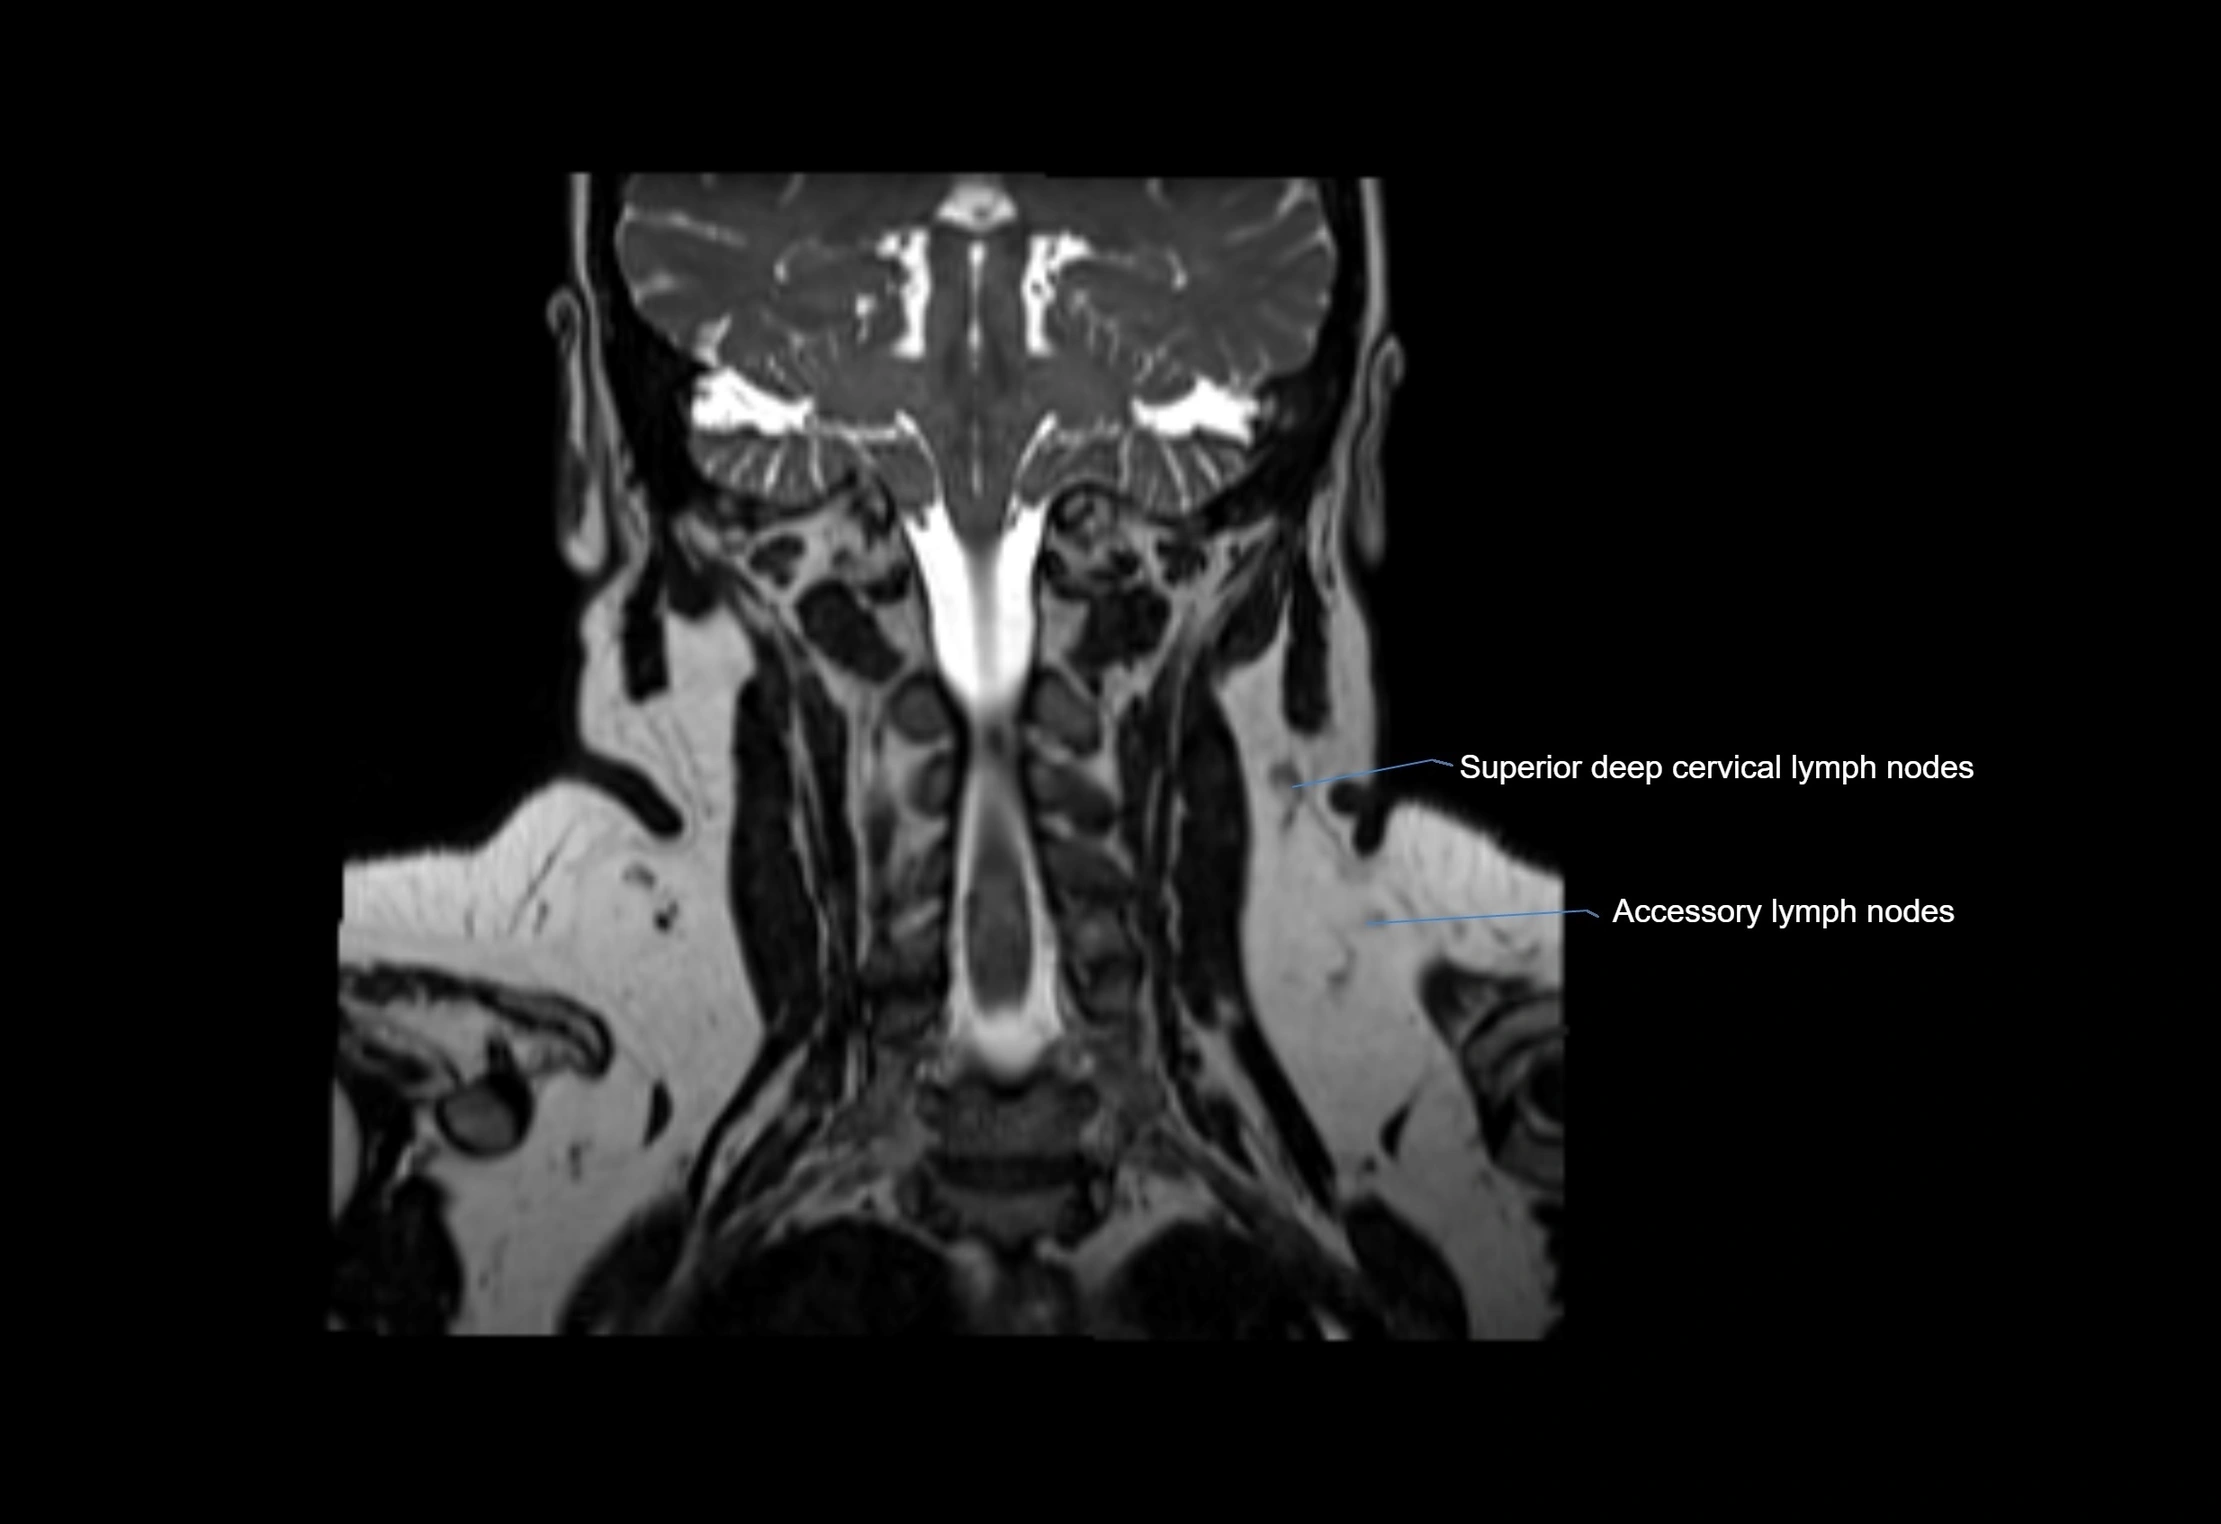

MRI Appearance

T1-weighted images:

• Normal accessory nodes appear as small, oval hypointense to intermediate signal structures within subcutaneous fat

• Surrounded by hyperintense fat, enhancing contrast for visualization

• Pathological nodes may appear enlarged or rounded, sometimes with cortical thickening

T2-weighted images:

• Nodes show intermediate signal, with surrounding fat bright

• Useful for detecting edema, inflammation, or infiltration

• Fatty hilum may appear slightly hyperintense relative to cortex

STIR (Short Tau Inversion Recovery):

• Fat suppression enhances visualization of edematous or pathological nodes

• Normal nodes appear low to intermediate signal, while inflamed or metastatic nodes appear hyperintense

• Useful for detecting subtle lymphadenopathy or early pathology

MRI images